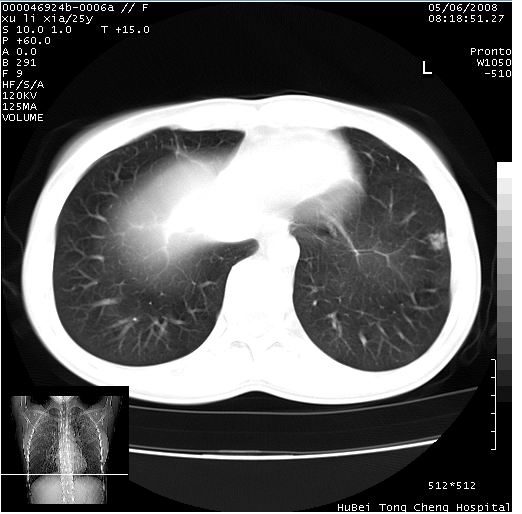

患者 女,25岁。因“左侧卵巢肿瘤”术前胸片偶然发现两肺病变。平素无明显不适,无呼吸系统症状及体征,无传染病史。

cr x线胸片提示:两肺感染性病变(结核可能性大)。

胸部ct轴位平扫(层厚10mm,螺距1.5,重建间隔10mm),图像如下:

(注:上级医院会诊胸部ct片——考虑为肺部真菌感染。)

病灶呈地图样分布于肺外围,与正常组织分界清晰+弥漫性磨玻璃影中见小叶间隔增厚呈碎石路样表现+年轻女性,无明显临床症状=肺泡蛋白沉积症?